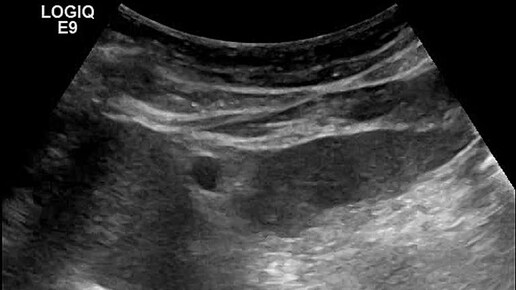

Видео к статье: "СЛУЧАЙ ДИАГНОСТИКИ СОЧЕТАННОЙ ПАТОЛОГИИ" Адрес: https://dzen.ru/a/aQRH94-8ajiog_3_

Ультразвуковые находки от врача УЗД Зорина Я.П.